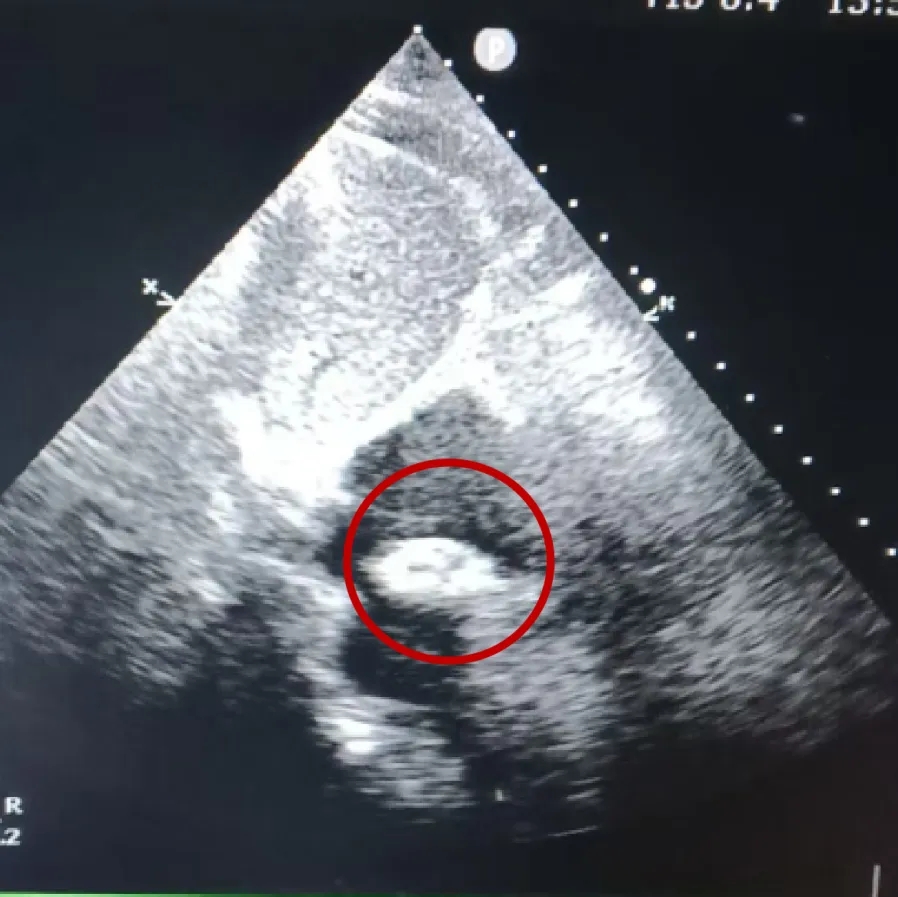

经胸超声描述:房间隔可见回声中断,胸骨旁大动脉短轴切面回声中断约14.0mm,断端与主动脉根部无明显边缘回声,心尖四腔心切面回声中断约16.8mm(除去软边),断端距二尖瓣前叶室间隔附着点约17.8mm,断端距房顶约11.7mm,房间隔全长约49.8mm,剑下双房心切面回声中断约13.3mm,剑下双房、双腔切面回声中断约12mm,房缺距上腔静脉入口较近,CDFI:房水平可见左向右分流信号。右心轻大。

超声提示:房间隔缺损(II孔型,距上腔静脉入口较近)、房水平左向右分流,右心轻大,肺动脉高压(轻度)。

四腔心切面

主动脉短轴切面

双房心切面

封堵器锁定成型后,超声下多切面确认封堵器盘面贴合,稳定夹持缺损